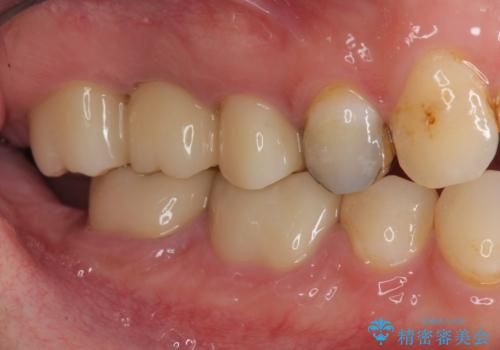

銀歯の下に大きな虫歯の再発

「 セラミック治療 」奥歯を白くしたい